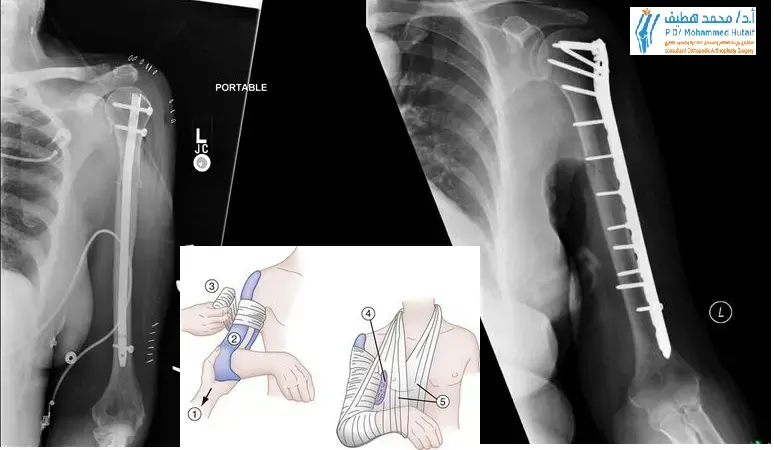

1. التثبيت الداخلي المفتوح والرد (Open Reduction and Internal Fixation - ORIF):

• تتضمن فتح الجلد والوصول مباشرة إلى موقع الكسر.

• يتم رد (إرجاع) الأجزاء المكسورة إلى وضعها التشريحي الصحيح.

• يتم تثبيت الكسر باستخدام ألواح (Plates)، ومسامير (Screws)، أو أسلاك معدنية (Wires).

• شائع الاستخدام لكسور جسم العضد والكسور المعقدة للطرف القريب والبعيد.

2. المسامير داخل النخاع (Intramedullary Nails):

• يتم إدخال مسمار معدني طويل مجوف داخل التجويف النخاعي لعظم العضد.

• يُستخدم بشكل أساسي لكسور جسم العضد.

• يوفر تثبيتًا مستقرًا مع إمكانية الشفاء البيولوجي الجيد.

• عملية التثبيت الداخلي (ORIF): خطوة بخطوة مع الأستاذ الدكتور هطيف

تعتبر عملية التثبيت الداخلي المفتوح والرد (ORIF) من العمليات الشائعة لكسور العضد. يقود الأستاذ الدكتور محمد هطيف هذه العمليات بدقة وخبرة فائقة، مع التركيز على استعادة التشريح الدقيق والوظيفة الكاملة.

4. التثبيت الداخلي (Internal Fixation):

• يتم استخدام ألواح معدنية ومسامير، أو مسامير داخل النخاع لتثبيت الأجزاء المكسورة معًا بشكل دائم.